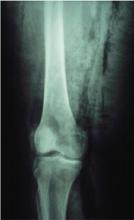

FIGURE 3

Radiograph of knee

Note the gas tracking down the patient’s leg, past areas of obviously clinical celulitis.

The decision to obtain x-rays of her pelvis and femur was made to assess the extent of her infection (FIGURES 2 AND 3).